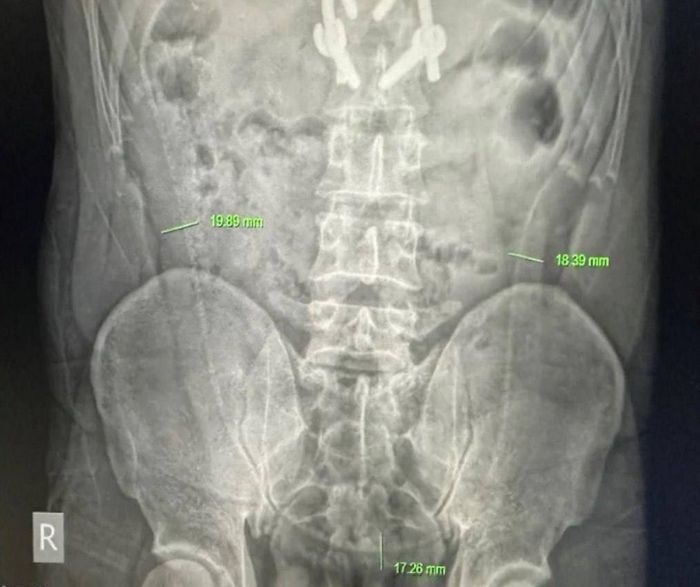

В больницу с острыми болями в животе поступил 31-летний мужчина. Рентген показал наличие внутри «длинной, похожей на кость структуры».